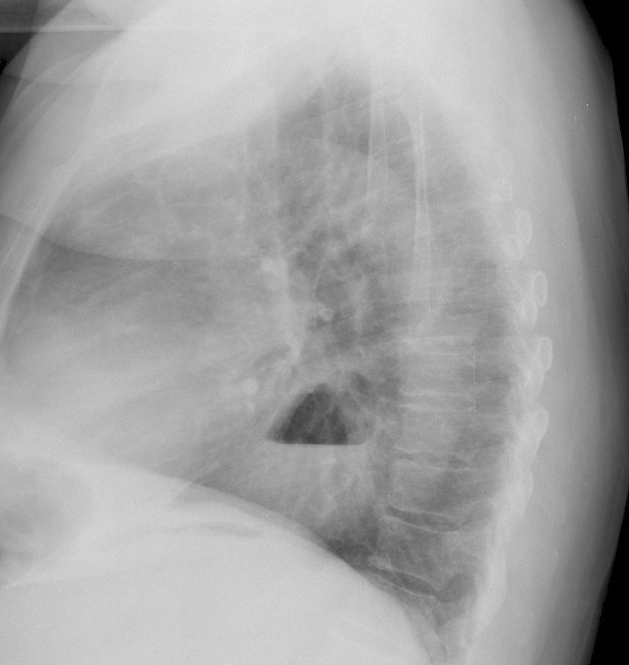

КТ-диагностика: Диафрагмальная грыжа в деталях